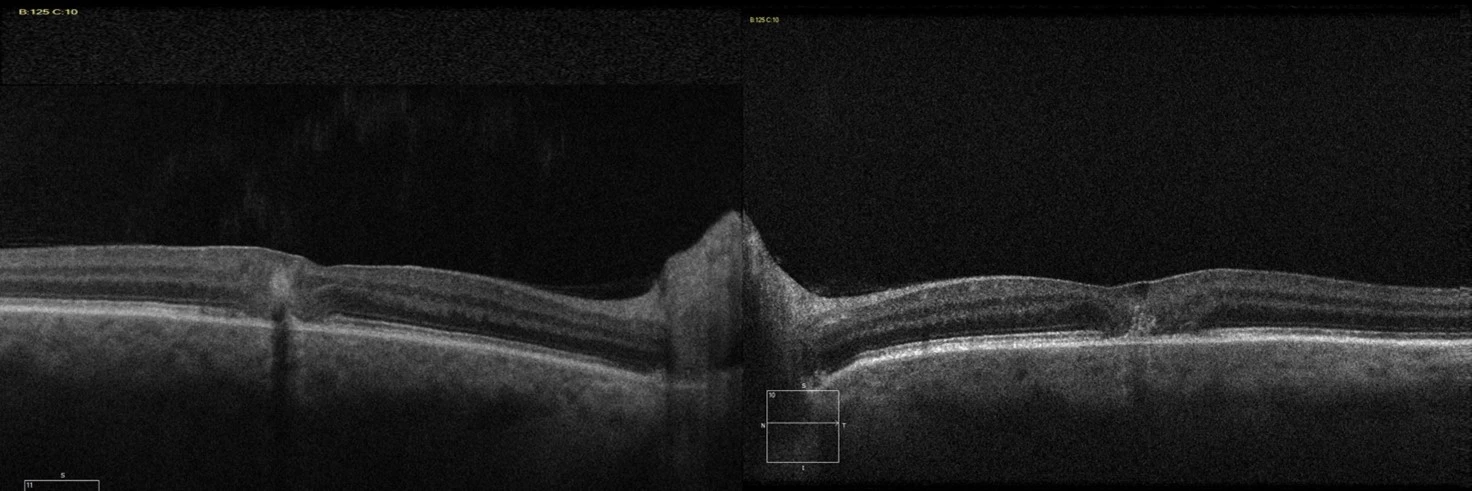

RVA 6/12, LVA 6/7.5. Clinical Exam of the retina displays loss of the foveal reflex, yellow crystalline spots and intra-retinal pigment hyperplasia (Figure 1 - above). OCT displays hypo-reflective inner retinal clefts, outer retinal atrophy and hyper-reflective spots (Figure 2). FFA demonstrates hyper-fluorescent capillaries temporal to the fovea (Figure 3).

Figure 2 - OCT

OCT typically displays hypo-reflective inner retinal clefts, outer retinal atrophy and hyper-reflective spots. Early FFA shows telangiectatic capillaries temporal to the fovea with late-phase diffuse hyper fluorescence. Disease progression may result in subretinal or intraretinal neovascularization, responsive to anti-VEGF therapy, however this treatment is ineffective in non-neovascular disease, MacTel Type 2 without neovascularisation.